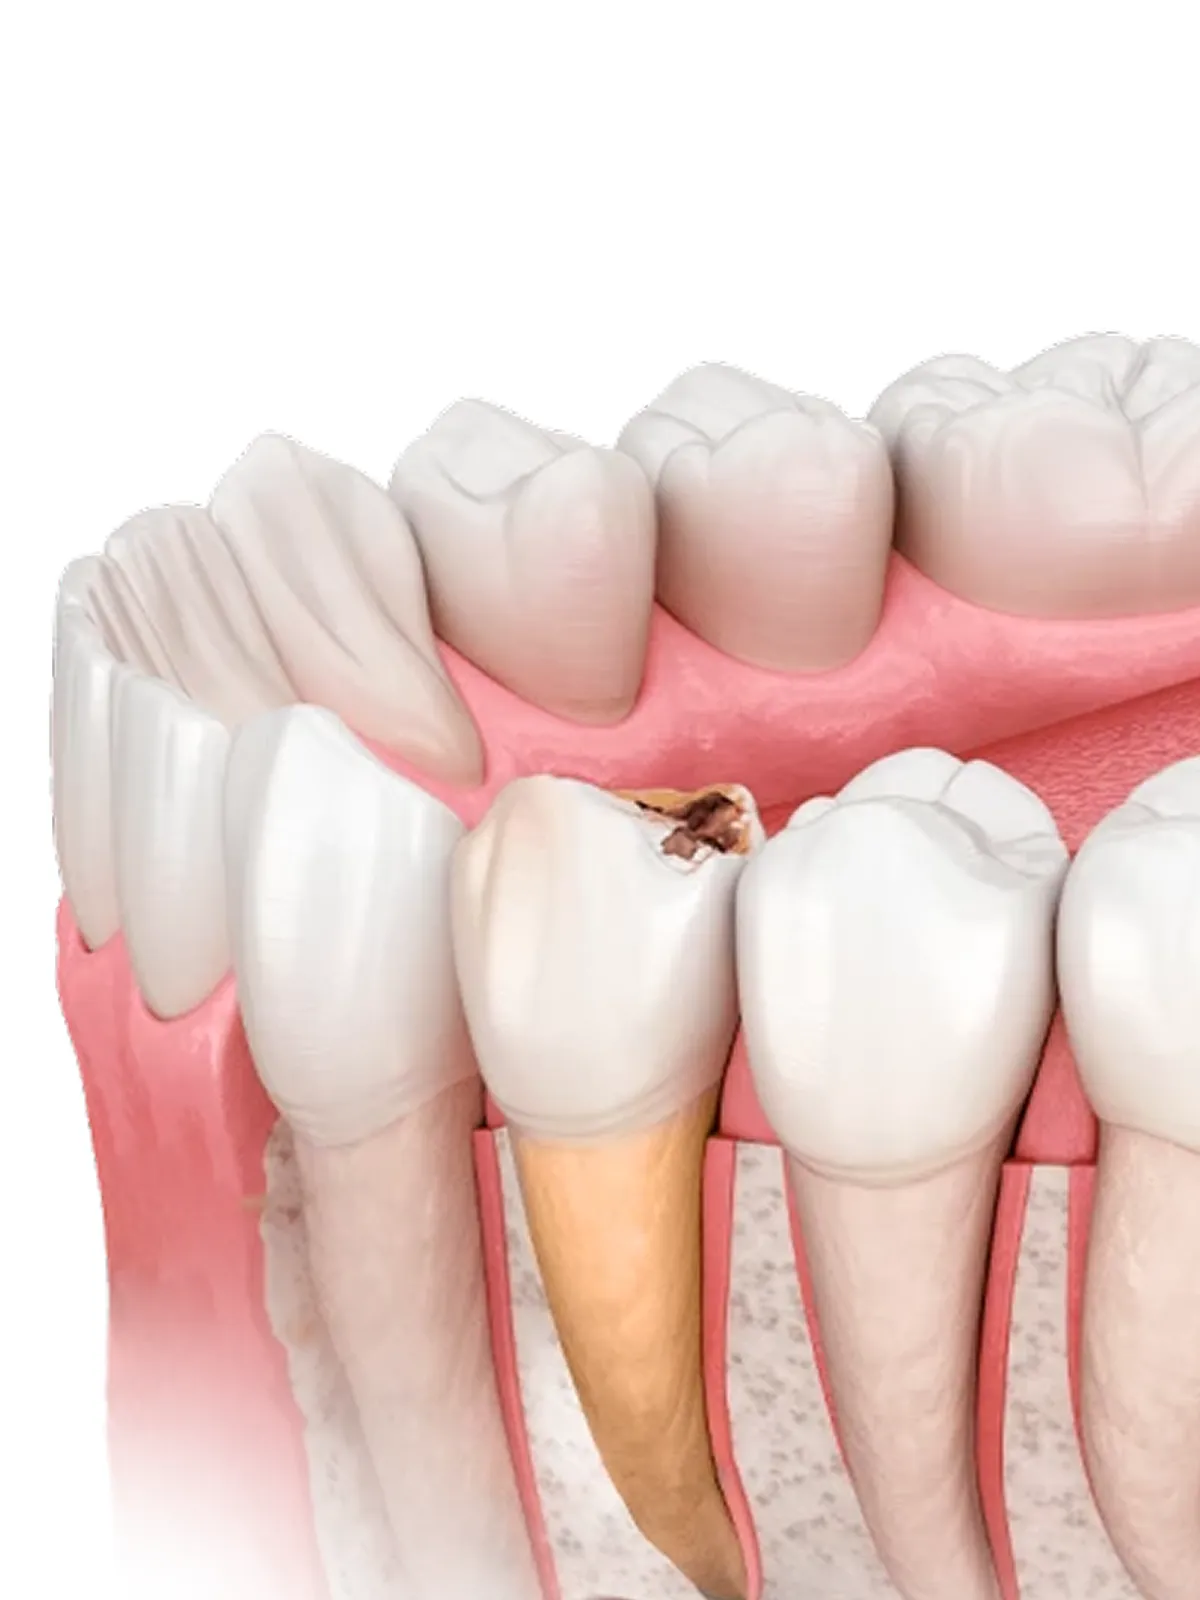

Удаление проводится только тогда, когда сохранить зуб невозможно или небезопасно.

Небольшой отёк — нормальная реакция после вмешательства. Врач объясняет, как он будет проходить и что делать, чтобы уменьшить дискомфорт.

Начальное заживление занимает несколько дней. Полное восстановление тканей требует больше времени и зависит от сложности удаления и индивидуальных особенностей.

Если боль или отёк усиливаются, появляется температура или сильное кровотечение — необходимо обратиться к врачу для осмотра.